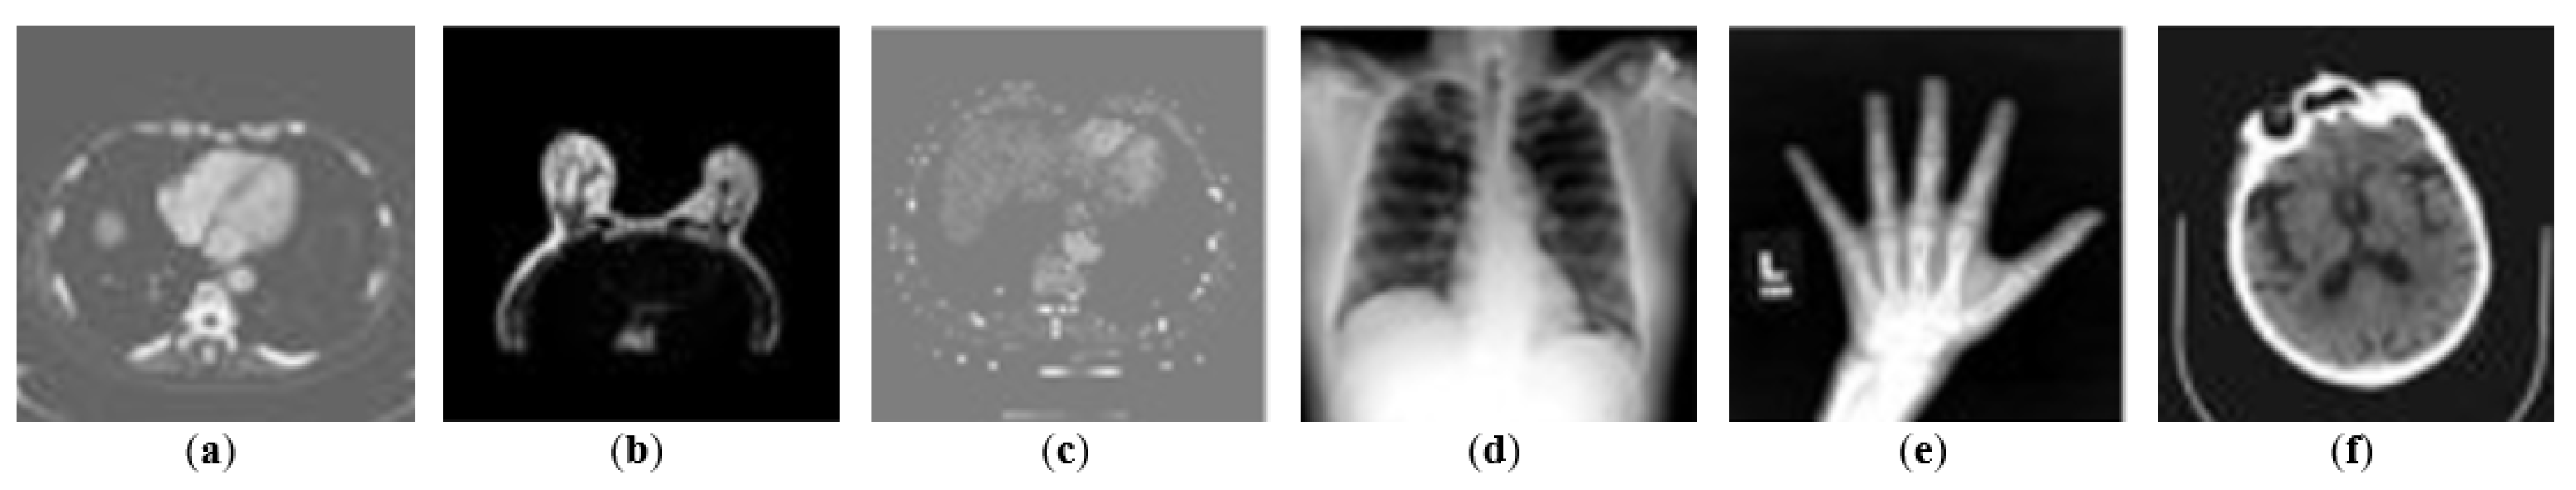

In the first attack configuration, the interceptor assumes that the targeted data contains medical images, but is unaware of their type (); therefore, the malicious actor trains the reconstruction model using a publicly available dataset with different medical-related classes. In the following experiments (see Section 3.3), the reconstruction model is trained using the Medical MNIST dataset [29]. It contains six classes of X-ray images (abdomen CT, breast MRI, CXR, chest CT, hand radiography, head CT), each class totalling around 7000 samples. All 40,954 medical images are used for training, and the evaluation is performed on the intercepted obfuscated dataset. The Medical MNIST images have a size of 64 × 64 pixels, but they are resized to 128 × 128, the dimensions of the frames sent by the hospital. Figure 9 depicts a sample of each category of the Medical MNIST dataset.

Figure 9.

Medical MNIST samples: abdomen CT (a), breast MRI (b), CXR (c), chest CT (d), hand radiography (e), head CT (f).